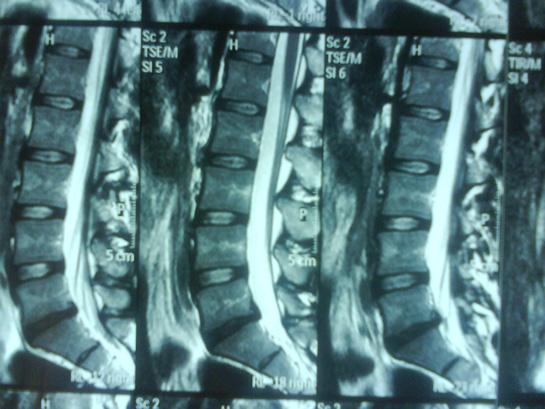

1 Hafta önceki MR ım Bulgular: LOMBER MR İNCELEMESİNDE ; Lomberlordoz düzleşmiştir. Posteriorvertebral hat düzgün ve kesintisiz olarak izlenmektedir. Vertebraların korpusyükseklikleri ve sinyal intensiteleri normaldir. Spinal kanal normal form vegenişliktedir. İntra spinal kitle lezyonu izlenmedi. İntervretebral disklerde hidrasyon kaybı izlendi. L2-L5 intervertebral disklerde posterior santral disk protrüzyonu izlendi. Bilateral sinir kökü basılıdır. Diğer intervertebraldisklerin yükseklikleri ve sinyal intensiteleri normaldir. Disk posteriorkonturları normal olup, dural kese ve nöral elemanlara bası saptanmadı. Ventralepidural yağlı doku ve nöral foramenler açıktır. Konusmedüllaris normal düzeyde ve sinyal intensitesi doğaldır. Paravertebralyumuşak dokulara ait patoloji saptanmadı. Sağ kalçada ağrı oluyor Zaman zaman da sol bacakta ağrı oluyor. genelde günlük 3-4 km yürüyüş yapıyorum Zaman zaman oturup dinleniyorum Değerlendirme rica ediyorum Teşekkür ederim

MR bulgularınıza göre, lomber lordozunuzda bir düzleşme gözlemlenmiş. Bu durum, sırt ve bel bölgesindeki kasların ve ligamentlerin dengesizliğinden kaynaklanabilir. Ayrıca, intervertebral disklerde hidrasyon kaybı ve L2-L5 arasında posterior santral disk protrüzyonu mevcut. Bu, bel bölgesindeki sinir köklerine baskı yaparak sağ kalçanızda ve zaman zaman sol bacağınızda ağrıya neden olabilir.